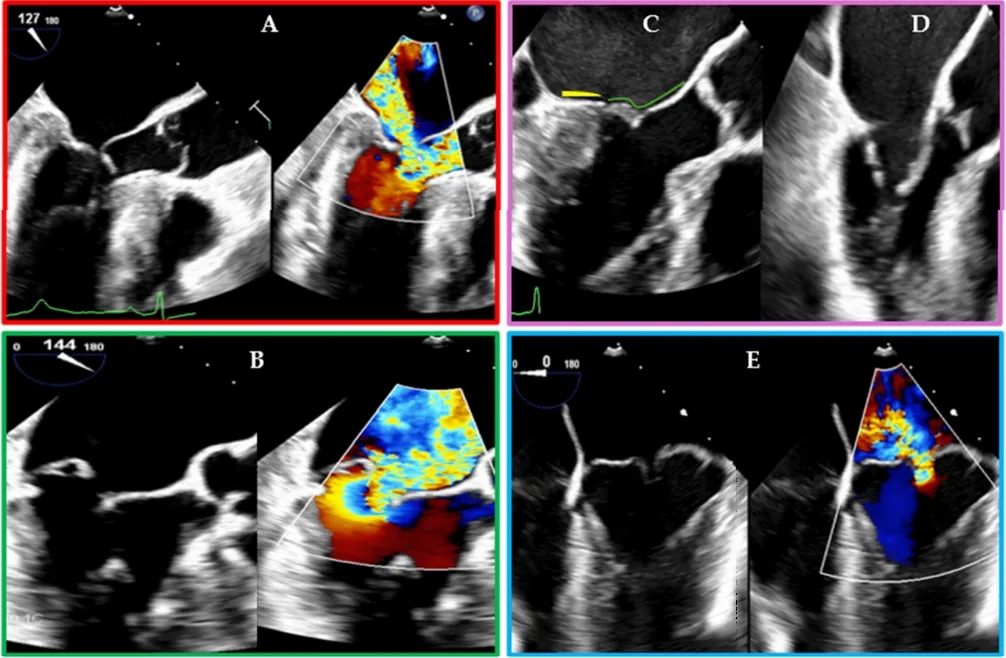

然而,患者选择仍然至关重要。微创二尖瓣修复术可能不适用于复杂的再次手术、严重胸壁畸形或广泛瓣环钙化的病例。该技术也存在学习曲线,需要具备术中经食管超声心动图(TEE)技能的心脏麻醉医师参与,不仅要明确识别二尖瓣病变(如图2所示)并指导手术,还要确保外周插管时导管定位正确。

图2.导致二尖瓣反流的不同二尖瓣病变的经食管超声心动图表现:(A)因室间隔基底段肥厚和左心室腔狭小导致二尖瓣叶收缩期前向运动引起的二尖瓣反流;(B)二尖瓣后叶(PML)脱垂引起的二尖瓣反流;(C)心房功能性二尖瓣反流病例:注意二尖瓣后叶的附着点(黄线)向后移位至左心室嵴上方,使其看起来较短,且接合区也向后移位;绿线描绘二尖瓣前叶;(D)风湿性二尖瓣疾病引起的二尖瓣反流病例:注意二尖瓣叶舒张期呈圆顶状;(E)二尖瓣前叶和后叶双叶脱垂引起的二尖瓣反流;(A、B、E)图同时显示二维模式和二维彩色多普勒图像。